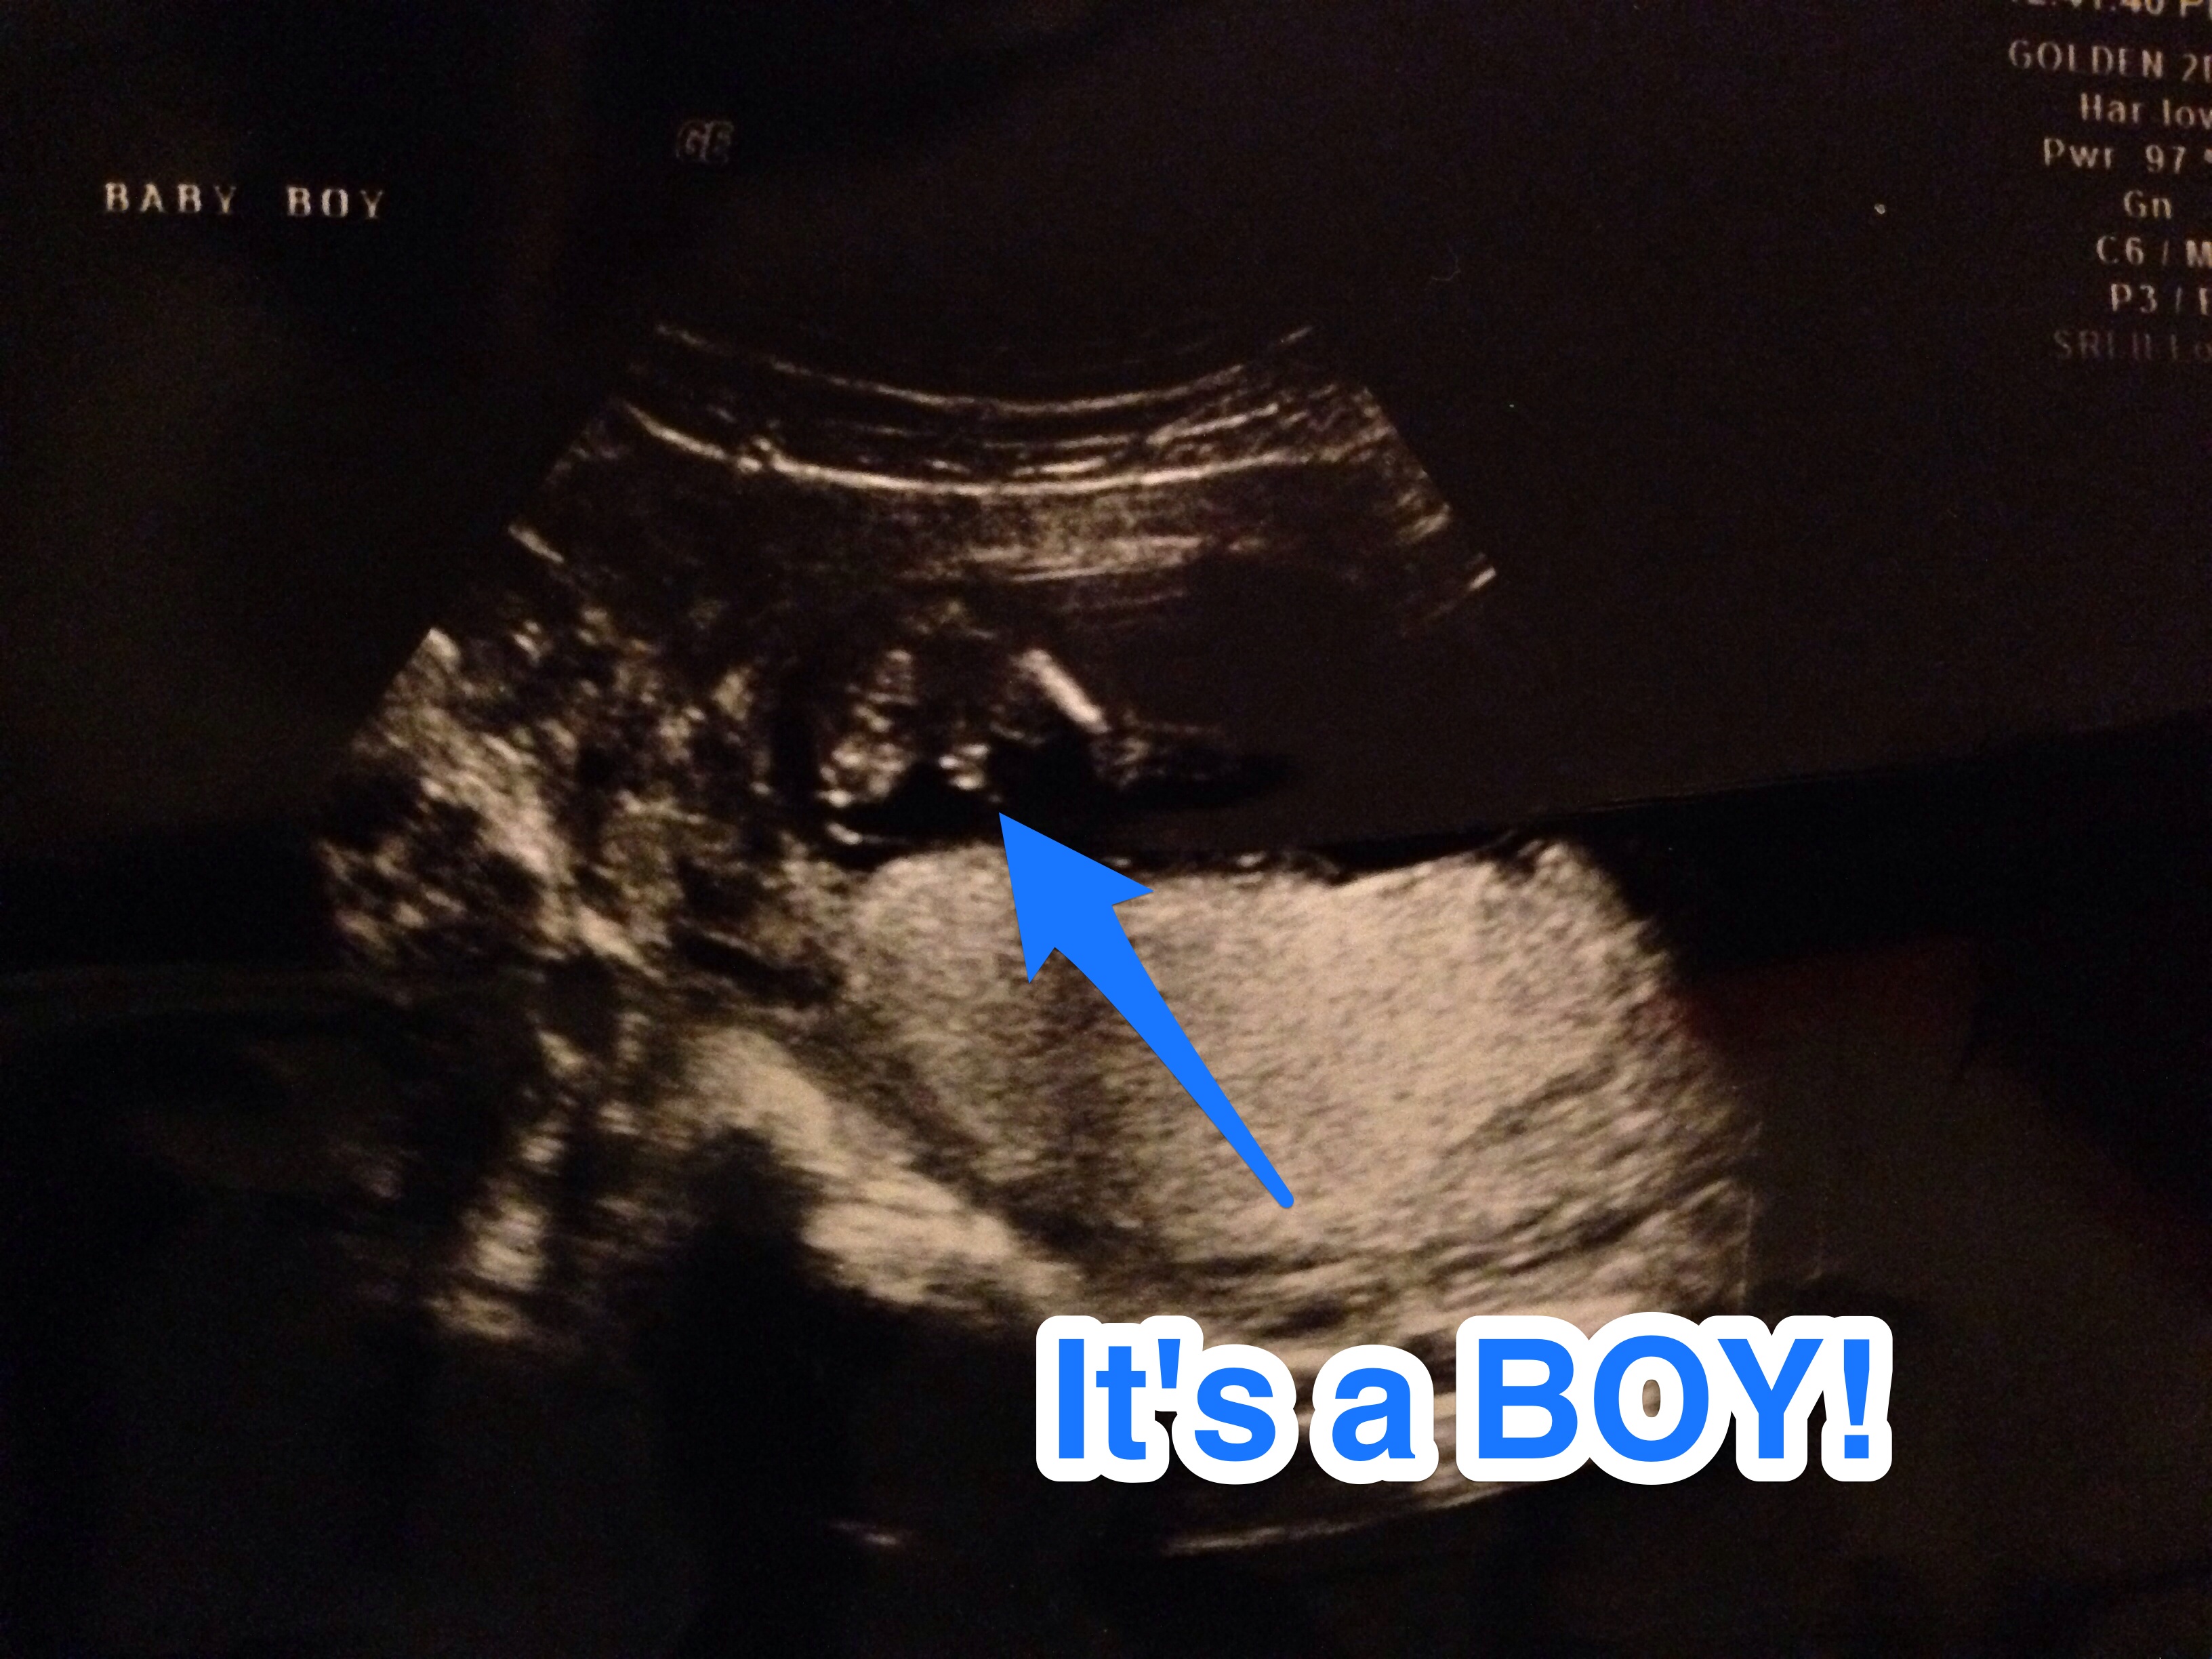

12w4d NT sono - boy or girl? I don't know how to do this